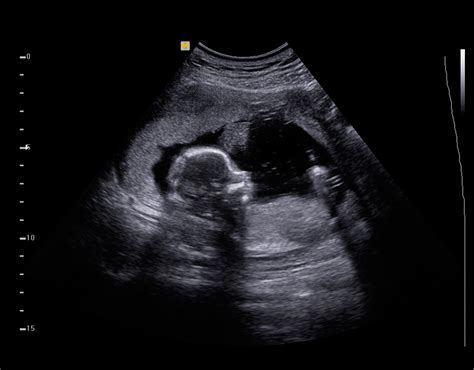

Discovering that you are pregnant is one of life’s most profound experiences, and for many parents-to-be, the first glimpse of their baby on a screen is a moment of pure magic. You have likely heard the term mentioned by friends, family, or your healthcare provider during early prenatal visits. But what is a sonogram, exactly, and why is it such an integral part of modern prenatal care? At its core, a sonogram—often referred to interchangeably as an ultrasound—is a medical imaging technique that uses high-frequency sound waves to create visual representations of the inside of the body. In the context of pregnancy, it provides a window into the womb, allowing doctors to monitor the development, growth, and health of the fetus.

The sonographer will then move the transducer firmly across your belly. You may feel slight pressure, but it should not be painful. As they scan, you will see grainy, black-and-white images on the screen. While these might look like indistinct shapes to the untrained eye, the professional performing the exam is trained to identify specific structures and measurements.

While seeing your baby moving on the screen is exciting, it is important to remember that a sonogram is a diagnostic tool, not a photo session. The images require clinical expertise to interpret. A technician, or sonographer, gathers the images, but a radiologist or your OB-GYN interprets them to ensure everything is progressing as expected. If the doctor notices something unexpected, they will discuss it with you directly. It is perfectly normal to have questions during the exam, and the sonographer will usually explain what they are looking for throughout the process.